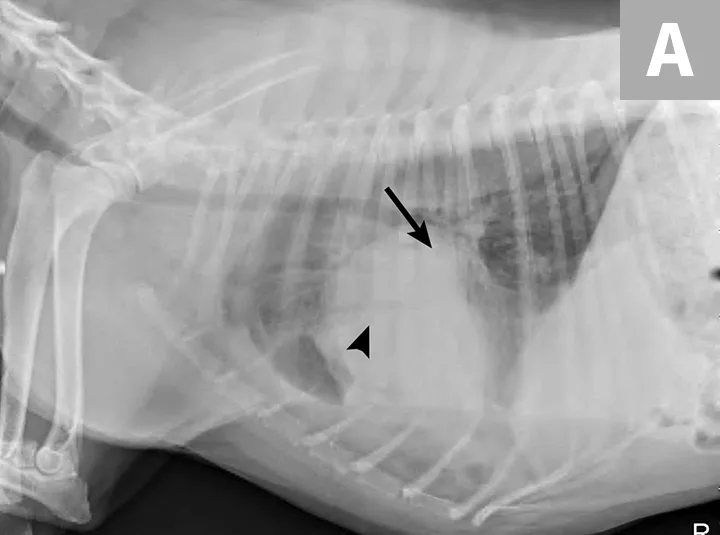

FIGURE 3A

Right lateral (A) and ventrodorsal (B) thoracic radiographs obtained after thoracocentesis showing improvement in pleural effusion with a persistent soft tissue opacity in the left mid-to-cranial thorax. An air bronchogram is seen extending cranially from the hilus (arrowhead) where a subtle bulge (arrow) is present.